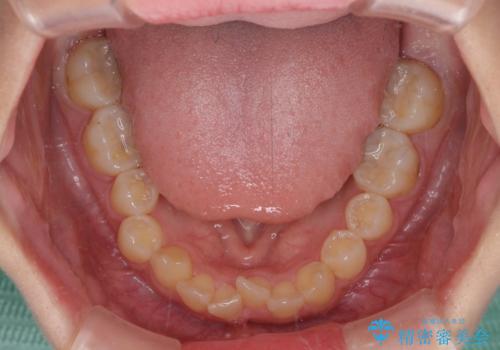

深い咬み合わせとデコボコの歯列をワイヤー矯正で改善

- 前歯のデコボコと深い咬み合わせを改善したいとのことで来院された患者様です。

下顎の装置が頻繁に脱落し、治療は難航しましたが、当初予定の2年間で無事に治療を終えることができました。